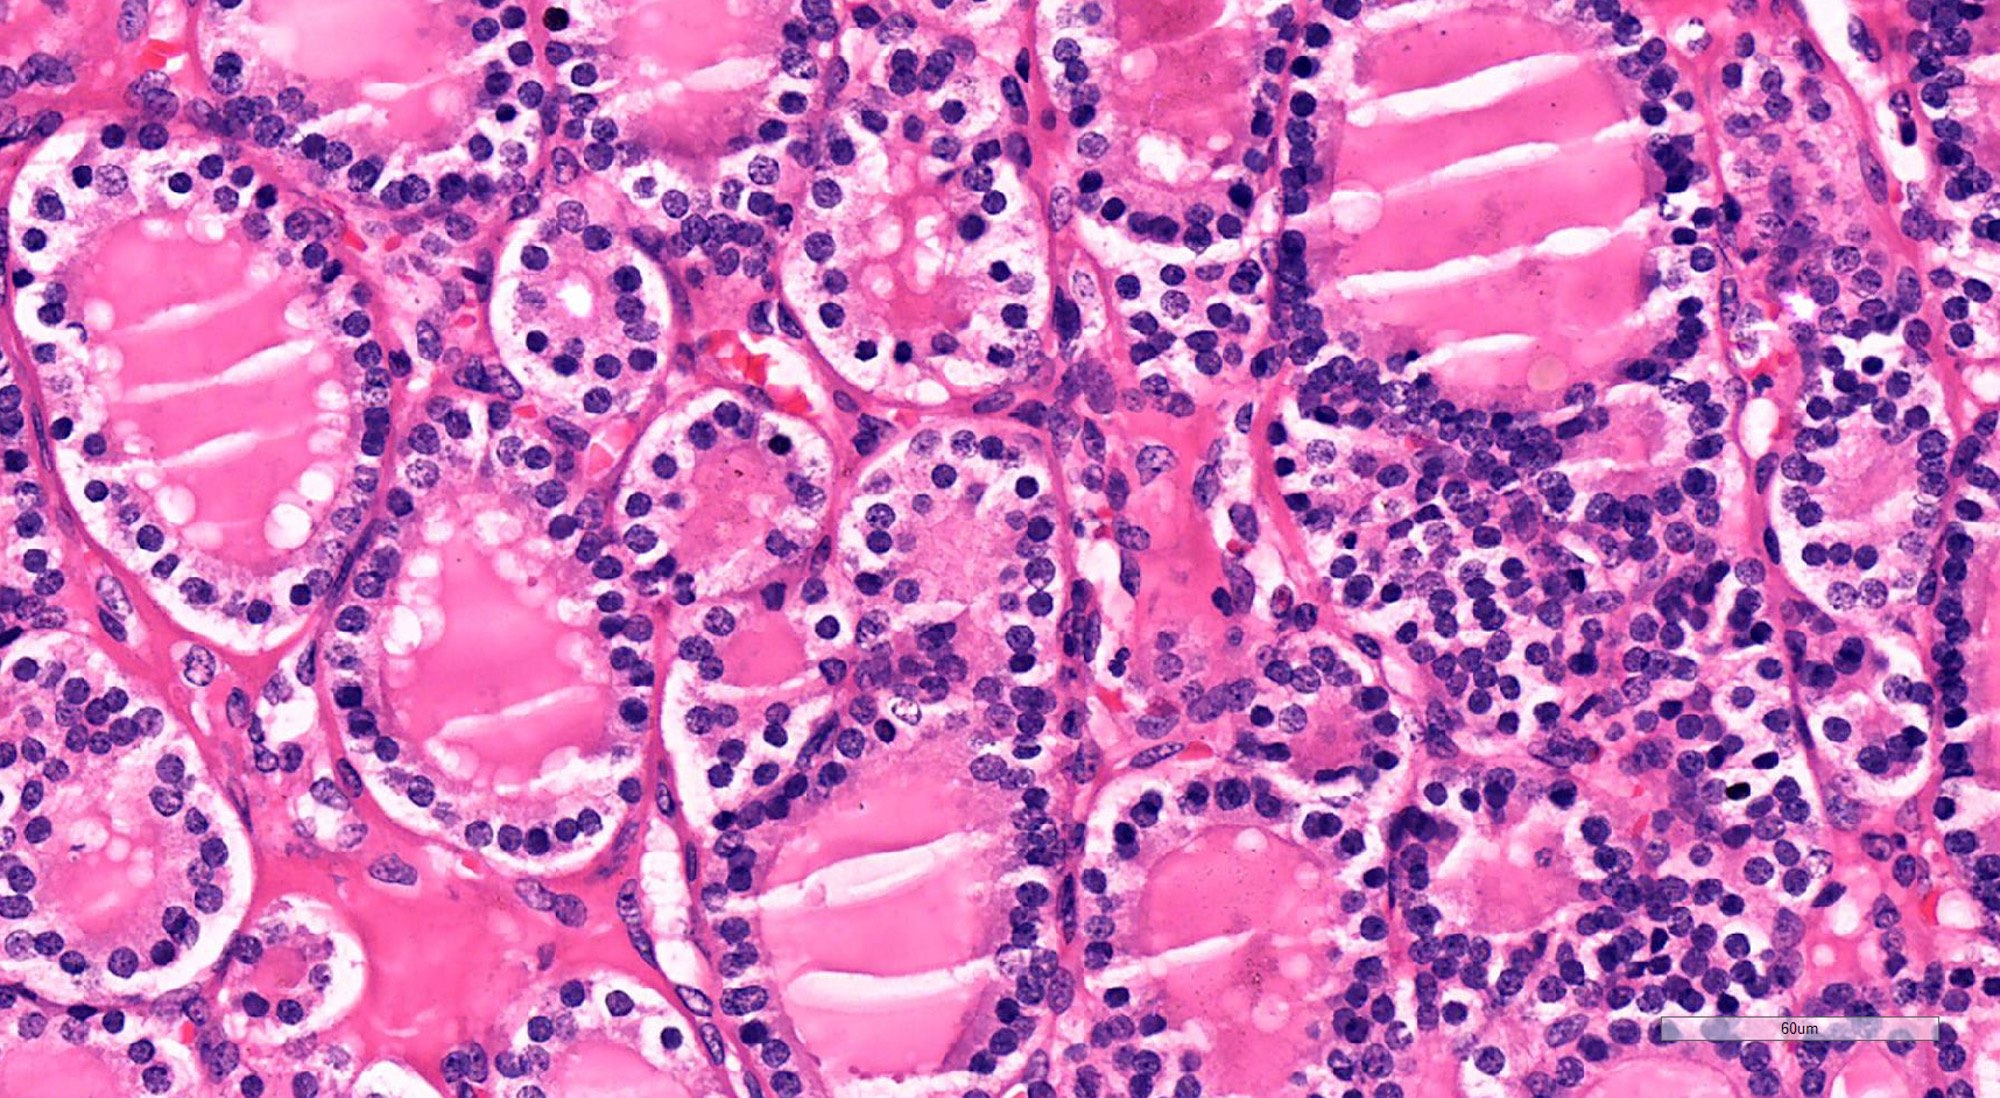

Microscopic (histologic) description

- Architecturally and cytologically different from surrounding gland

- Compression signs in surrounding thyroid tissue

- Encapsulated; thin or moderately thick capsule

- Architectural patterns (can be seen in any combination)

- Normofollicular (simple): size similar to normal thyroid follicles

- Microfollicular (fetal): smaller follicles, small amount of intraluminal colloid

- Macrofollicular (colloid): large follicles, flattened epithelium, abundant colloid

- Solid / trabecular (embryonal): minimal or no colloid

- Focal papillary pattern, occasionally; especially in hyperfunctioning adenoma and follicular adenoma with papillary hyperplasia

- Cuboidal to low columnar cells

- Small round nuclei, smooth nuclear boundary, uniformly hyperchromatic or euchromatic, dense chromatin, absent nuclear features of papillary thyroid carcinoma, nuclear score 0 or 1 (JAMA Oncol 2016;2:1023)

- Inconspicuous nucleoli

- Rarely, lipid filled vacuoles in cytoplasm

- Mitoses are uncommon

- Scant stroma

- Secondary changes: fibrosis, hyalinization, hemorrhage, hemosiderin deposition, edema, cystic degeneration, calcification, osseous or cartilaginous metaplasia

Microscopic (histologic) images

Contributed by Shipra Agarwal, M.D., Andrey Bychkov, M.D., Ph.D., Mark R. Wick, M.D., Asmaa Gaber Abdou, M.D. and AFIP

Patterns: